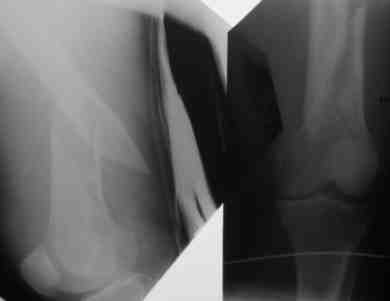

Рг в приложении.

Снимки вполне симпатичные. Единственное, по ротации не понял, уж больно неразборчивый тот, который без гвоздя.